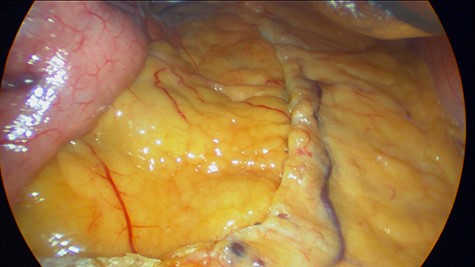

Patient is a 43-year-old female with past medical history of hypothyroidism and obesity. She sought surgical consultation since her body mass index (BMI) was high (36) and she had failed numerous attempts to lose weight over the past 10 years. Preoperative exams including an upper endoscopy were normal. LGS was planned. During the procedure, we used one 15 mm port, one 12 mm port and three 5 mm ports. A 30 telescope was used during the procedure to achieve visualization of the angle of his, a grasper was used as a liver retractor and a 36 French bougie was inserted to decompress the stomach. The incisura was located and a small window in the lesser sac was created 4 cm away from the incisura, the omentum was mobilized cranially, the bougie was advanced to the first part of the duodenum and staplers were used to create the sleeve. (Fig. 1) After this, the staple line was reinforced using a 3-0 synthetic absorbable monofilament suture (PDS 3-0, Ethicon, Johnson & Johnson). The specimen was retrieved from the 15 mm port, and the procedure was completed without complications. During the procedure, no lymph nodes or masses were seen. The patient underwent full recovery and was discharged without any apparent complications. Five days later, pathology reported that on the specimen, a small 4-mm polyp was detected in the staple line in the upper part of the fundus, a finding that was not detected on the previous endoscopy. After further evaluation, a grade II well-differentiated multifocal neuroendocrine tumor with vascular and perineural invasion was detected. Ki 67 index was 17% and 3/10 hpf mitosis were discovered (Figs 2, 3A and B).

(A) Pathology, gastric mucosa, (B) pathology, tumor invading the gastric muscle.